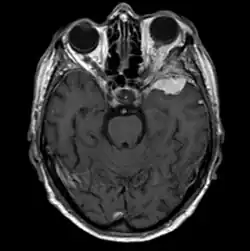

Sphenoid wing meningioma

Sphenoid wing meningiomas are diagnosed by the combination of suggestive symptoms from the history and physical and neuroimaging by magnetic resonance imaging (MRI) or computer averaged tomography (CT). Tumors growing in the inner wing (clinoidal) most often cause direct damage to the optic nerve leading especially to a decrease in visual acuity, progressive loss of color vision, defects in the field of vision (especially cecocentral), and an afferent pupillary defect. If the tumor continues to grow and push on the optic nerve, all vision will be lost in that eye as the nerve atrophies. Proptosis, or anterior displacement of the eye, and palpebral swelling may also occur when the tumor impinges on the cavernous sinus by blocking venous return and leading to congestion. Damage to cranial nerves in the cavernous sinus leads to diplopia. Cranial nerve VI is often the first affected, leading to diplopia with lateral gaze. If cranial nerve V-1 is damaged, the patient will have pain and altered sensation over the front and top of the head. Horner's syndrome may occur if nearby sympathetic fibers are involved.

Tumors found in the external third of the sphenoid are of two types: en-plaque and globoid meningiomas. En plaque meningiomas characteristically lead to slowly increasing proptosis with the eye angled downward. Much of this is due to reactive orbital hyperostosis. With invasion of the tumor into the orbit, diplopia is common. Patients with globoid meningiomas often present only with signs of increased intracranial pressure. This leads to various other symptoms including headache and a swollen optic disc. The differential diagnosis for sphenoid wing meningioma includes other types of tumors such as optic nerve sheath meningioma, cranial osteosarcoma, metastases, and also sarcoidosis. Following the physical exam, the diagnosis is confirmed with neuro-imaging. Either a head CT or MRI with contrast such as gadolinium is useful, as meningiomas often show homogenous enhancement. Angiography looking for signs like stretched arteries may be used to supplement evaluation of vascular involvement and to determine whether embolization would be helpful if surgery is being considered.